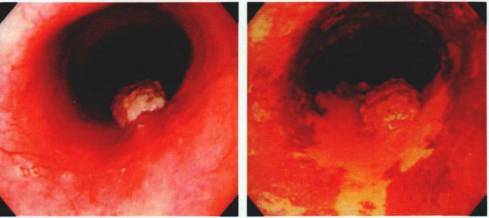

左图为IV型,IPCL形态扭曲,管径不一;右图为V1型,IPCL扭曲、扩张、形态不一、口径不等

左图为V2型,IPCL较V1型延长;右图为V3型 IPCL高度破坏、消失,边缘尚有部分IPCL存在,箭头所指为肿瘤血管(毛糙、扭曲)